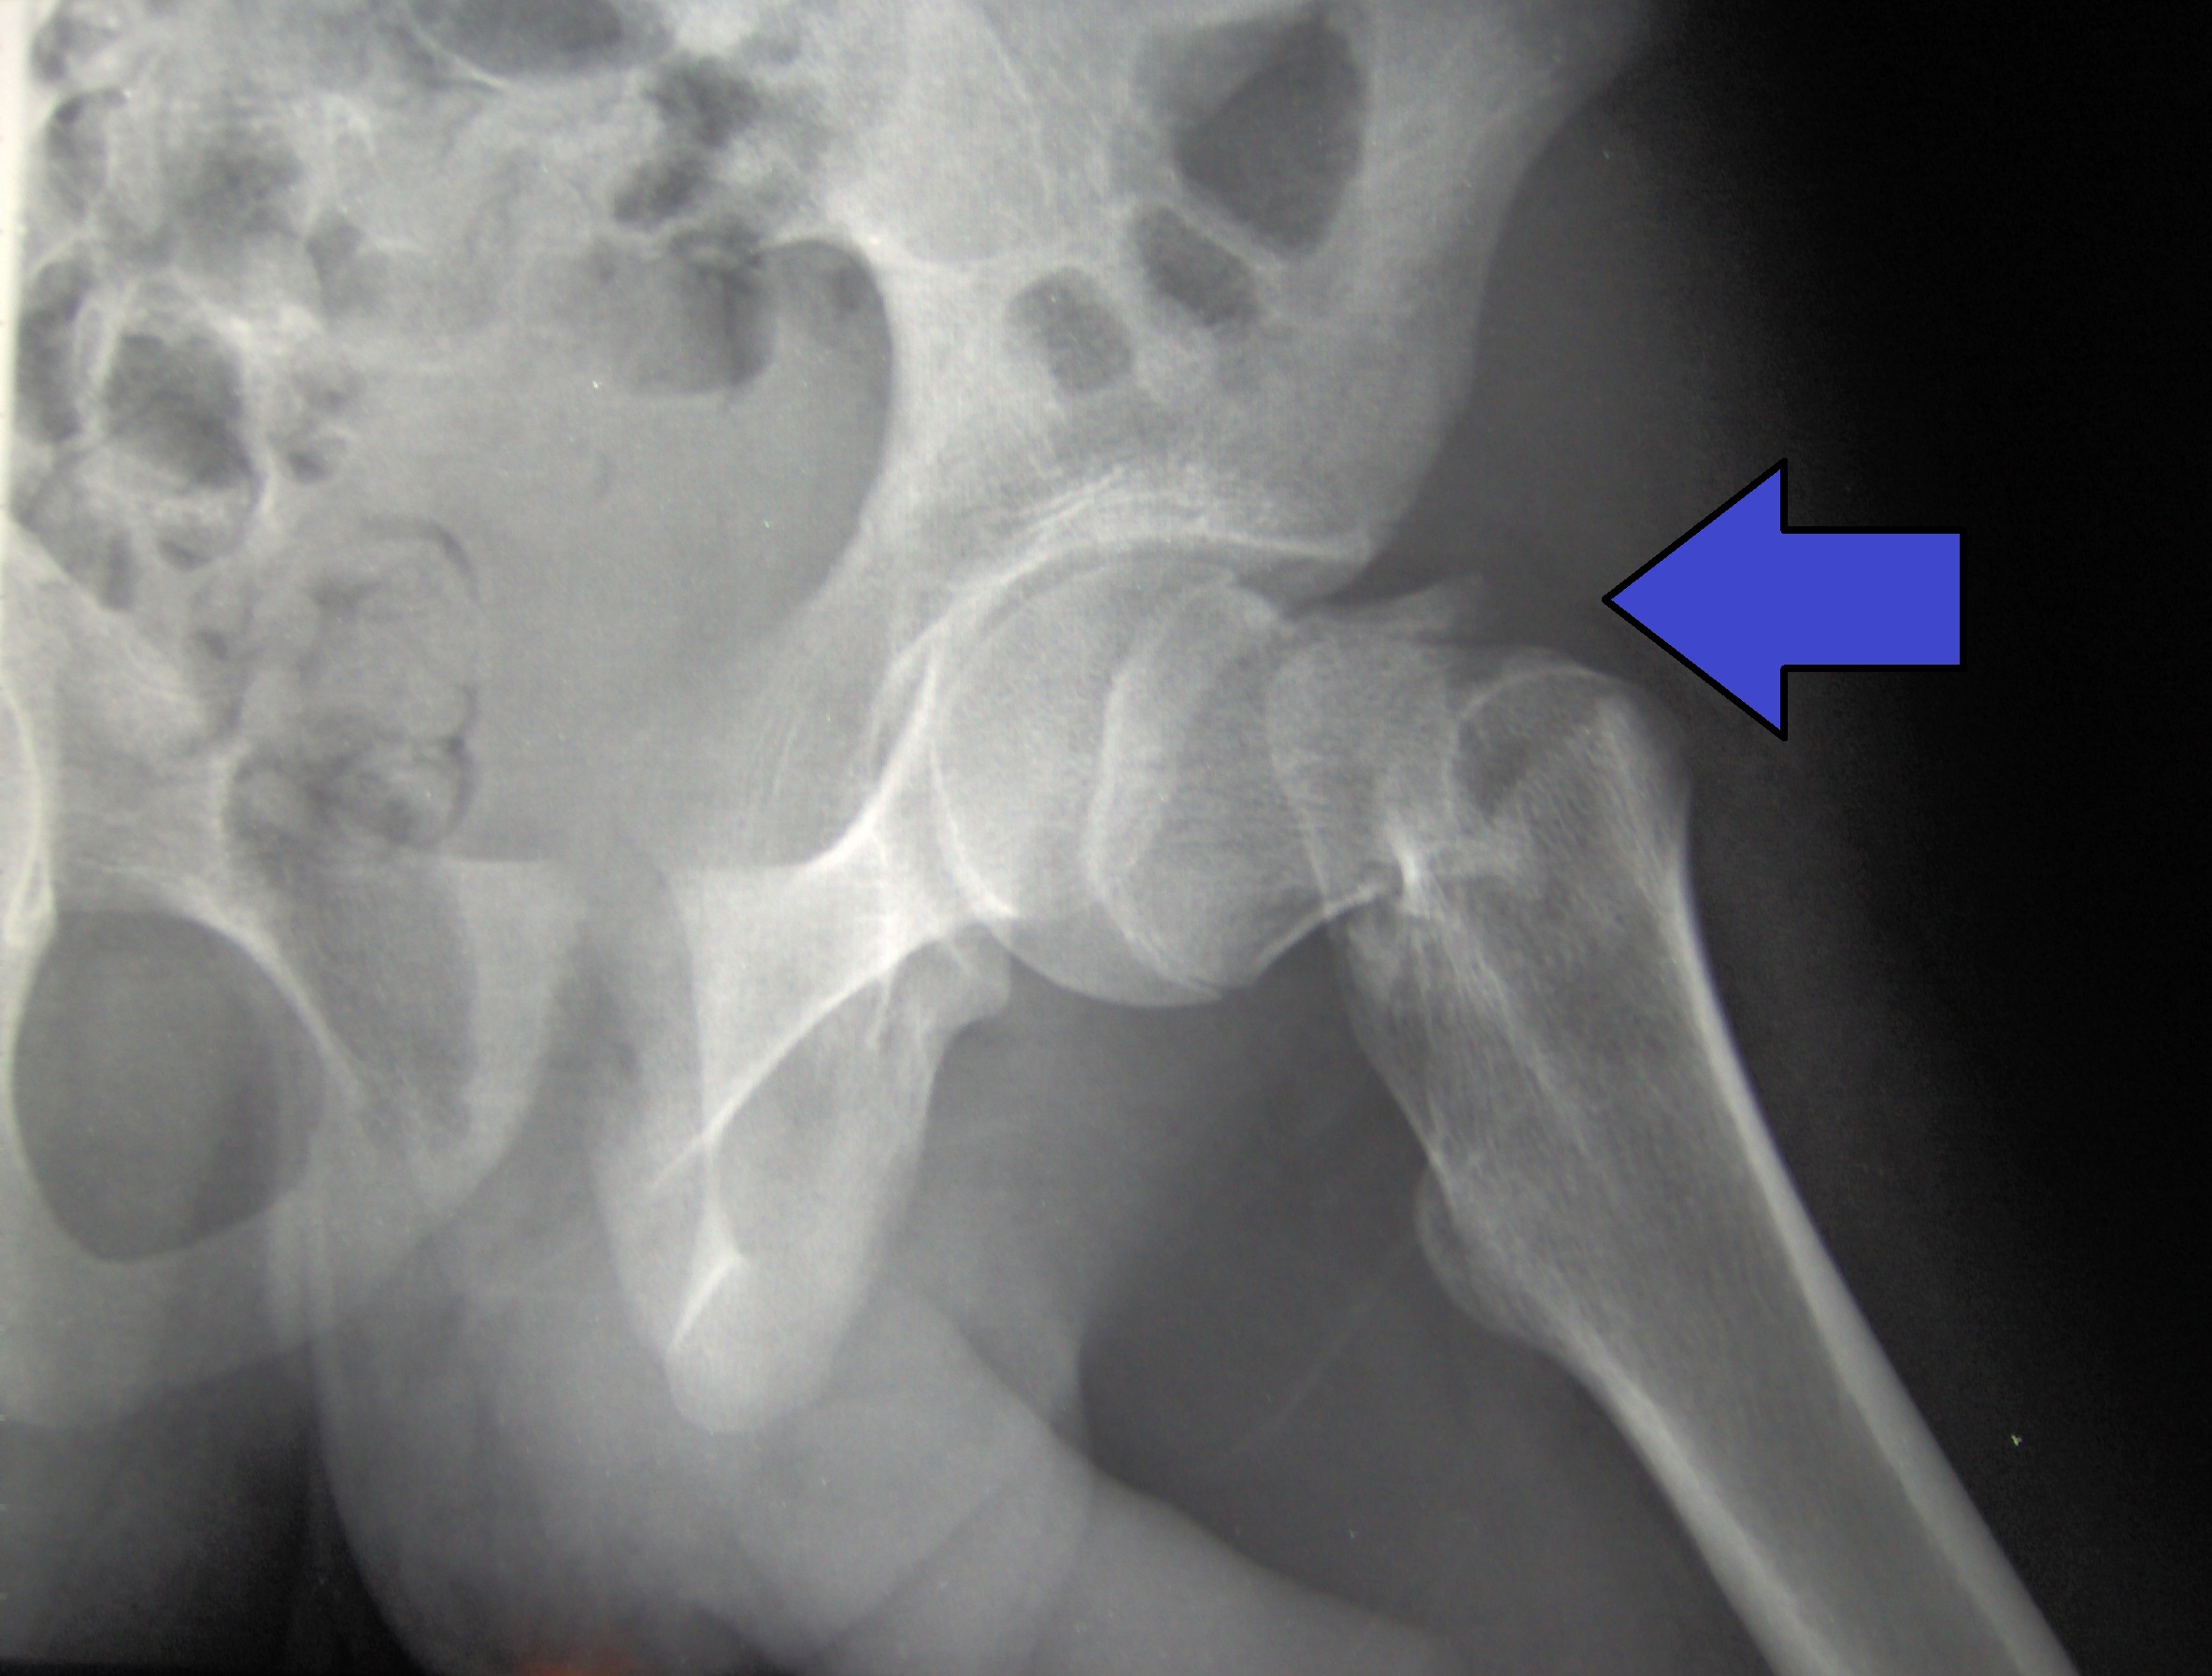

Rastreo para prevención de las fracturas por fragilidad: guía de Canadá

Para personas sin tratamiento preventivo actual de fracturas, la estrategia de realizar primero la evaluación del riesgo con la herramienta FRAX en mujeres de 65 años o más facilita la toma de decisiones compartida y permite a las pacientes considerar la farmacoterapia preventiva dentro de su contexto de riesgo individual (antes de la densitometría). La recomendación contra la detección en hombres y mujeres más jóvenes enfatiza la importancia de la buena práctica clínica. Canadian Medical Association Journal, 8 de mayo de 2023.